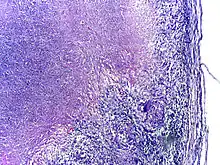

Tuberculosis is classified as one of the granulomatous inflammatory diseases. Macrophages, epithelioid cells, T lymphocytes, B lymphocytes, and fibroblasts aggregate to form granulomas, with lymphocytes surrounding the infected macrophages. When other macrophages attack the infected macrophage, they fuse together to form a giant multinucleated cell in the alveolar lumen. The granuloma may prevent dissemination of the mycobacteria and provide a local environment for interaction of cells of the immune system.[62] However, more recent evidence suggests that the bacteria use the granulomas to avoid destruction by the host's immune system. Macrophages and dendritic cells in the granulomas are unable to present antigen to lymphocytes; thus the immune response is suppressed.[63] Bacteria inside the granuloma can become dormant, resulting in latent infection. Another feature of the granulomas is the development of abnormal cell death (necrosis) in the center of tubercles. To the naked eye, this has the texture of soft, white cheese and is termed caseous necrosis.[62]